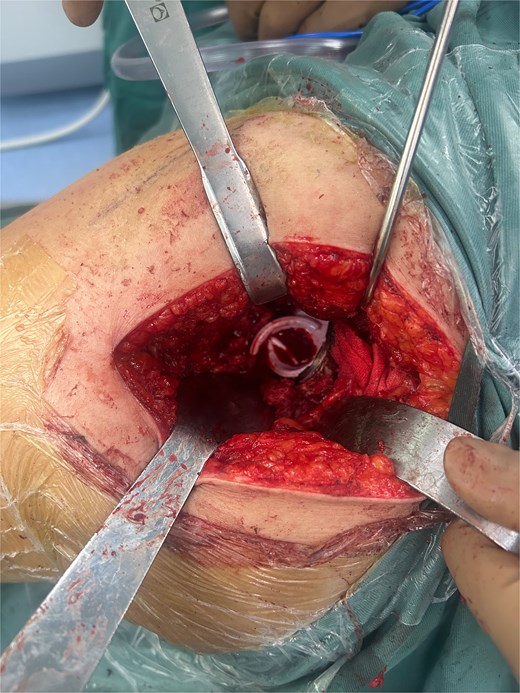

A 47-year-old woman, weighing 65 kg with a height of 158 cm and a body mass index (BMI) of 26 kg/m2, came to our hospital with chief complaints of bilateral hip pain and difficulty walking for 1 year and underwent left THA and 1 week of right THA because of bilateral avascular necrosis and collapse. X-ray of the pelvis of both hips revealed bilateral avascular necrosis and collapse (Fig. 1). A posterolateral approach was used for the bilateral hips in the lateral decubitus position. The implant consists of a Pinnacle cup (DePuy), DELTA ceramic liner and ceramic femoral head (BIOLOX DELTA), and collarless Corail stem (DePuy). After fixation of the acetabular cup, the senior surgeon placed the ceramic liner into the metal shell by hand. Unfortunately, the liner was not placed in the centre position and became stuck. The edge of the tilted ceramic is slightly greater than the cup, perhaps only 5 mm or less. The surgeon attempted to remove the liner by tamping the edge with the plastic impactor using light force several times, but the process of doing so fractured the ceramic liner (Fig. 2). The alumina ceramic fragment of the liner was removed carefully (Fig. 3), and the site was irrigated well. A 32-mm polyethylene liner and a ceramic femoral head were implanted. Full weight-bearing was allowed on postoperative day 1 with a walking aid. The patient remained hospitalized for 8 days to monitor closely for early perioperative complications. Sutures were removed on the seventh day, and the laboratory results indicated an absence of infection. At the 2-month postoperative interval, the patient achieved a successful outcome, with complete resolution of her preoperative symptoms as well as a return to all her activities of daily living (Fig. 4).